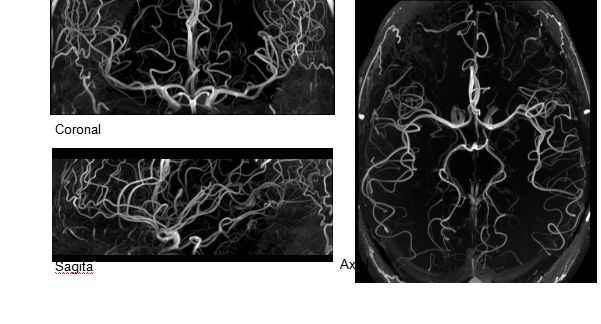

MAGNETOM Terra在業(yè)界首次實(shí)現(xiàn)了兩倍于傳統(tǒng)7T的超強(qiáng)梯度性能,實(shí)現(xiàn)超快速、超高效、超高分辨功能磁共振成像。如此高性能的梯度系統(tǒng)無論對(duì)于科研還是臨床都帶來了更多可能。

1毫米的各向同性分辨率DTI:神經(jīng)纖維束的交叉細(xì)節(jié)顯示

0.8毫米的各向同性分辨率:精確劃分灰質(zhì)和白質(zhì)

0.8毫米的各向同性分辨率:超精細(xì)的解剖細(xì)節(jié),例:小腦的精細(xì)結(jié)構(gòu)

超精細(xì)的解剖細(xì)節(jié):T2對(duì)比

0.17 x 0.17 x 0.8毫米分辨率超高。

(TOF)300微米的各向同性分辨率顯示最小的血管